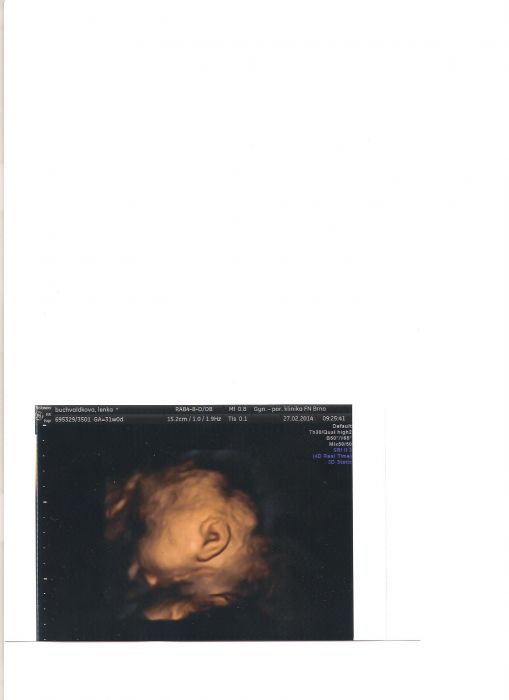

Holky musím se s Váma podělit po dlouhé době o srandu...tak dneska říkám doktorce...neodejdu dřív, než udělaáme nějakou fotku..tak jsme malou asi 15 minut natřepávali v bříšku a ona potvora nám celou bobu ukazovala jen ucho :-)))) No ...má ho pěkný :-) Posílám fotku ...